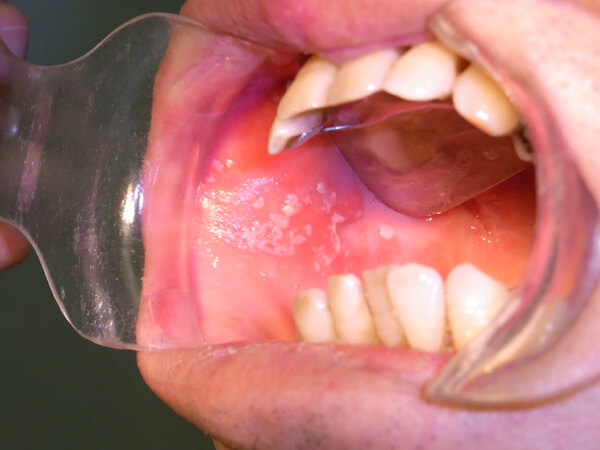

口腔カンジダ症

おもにカンジダ・アルビカンスという真菌(カビ)によっておこる口腔感染症です。口腔内に白苔を形成しますが、ガーゼで拭うと剥離可能です。しかし、中には剥離しにくいものもあります。